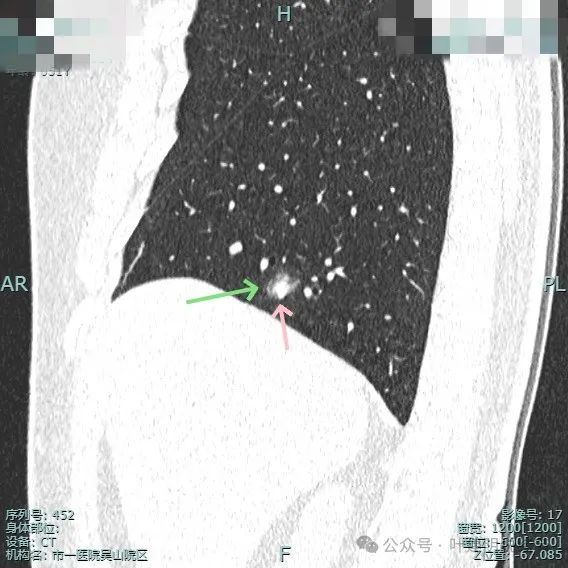

靶重建显示边缘细毛刺、外围磨玻璃密度,中间实性成分明显,表面不平有浅分叶。

中间实性成分感觉边缘较清,缺乏收缩力,外围的磨玻璃成分整体轮廓较清,边缘有细毛刺征。

明显的血管进入与异常增粗。

灶内密度杂乱,血管进入与增粗,表面不平。